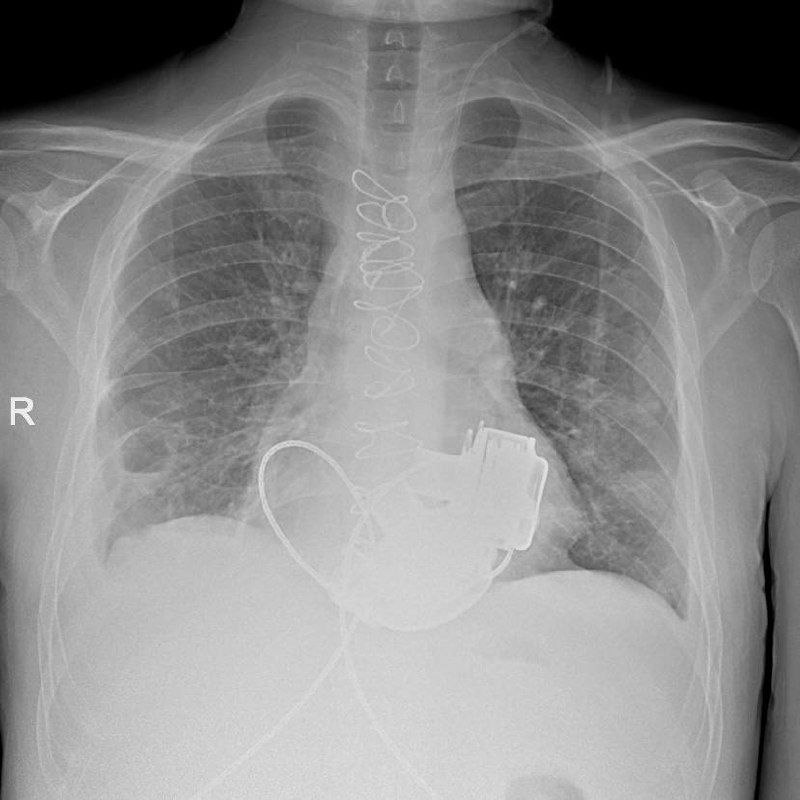

В Мариинской больнице готовится к выписке уникальный пациент. Как сообщил городской комитет по здравоохранению, в конце ноября 2025 года мужчине впервые в России имплантировали сразу два искусственных желудочка сердца.

Обычно пациенту вживляют одно такое устройство, но в этом случае потребовались сразу два прибора. Операцию провела бригада хирургов под руководством академика РАН Геннадия Хубулавы. Самым сложным, по словам специалистов, была синхронизация работы двух искусственных желудочков, но с этой задачей врачи успешно справились. Сейчас состояние пациента стабильное, что позволяет планировать его выписку из стационара.